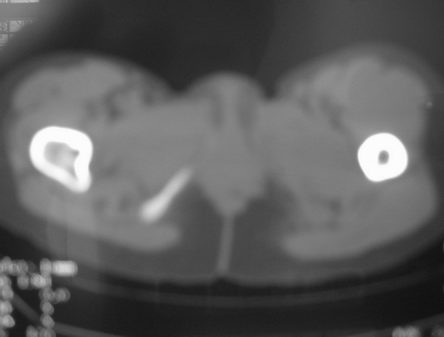

右股骨骨巨细胞瘤

女,31岁,右髋部疼痛半年,加剧两天不能行走

hhcckk发言:右股骨颈囊状骨质破坏,骨皮质变薄,周围硬化边不明显

拾荒者分析:该病例囊肿透亮度较高,骨膨胀轻微,还是要首先考虑骨囊肿。至于与骨细胞瘤的鉴别,影像鉴别困难。我想,发病年龄及临床症状可能是主要参考点。